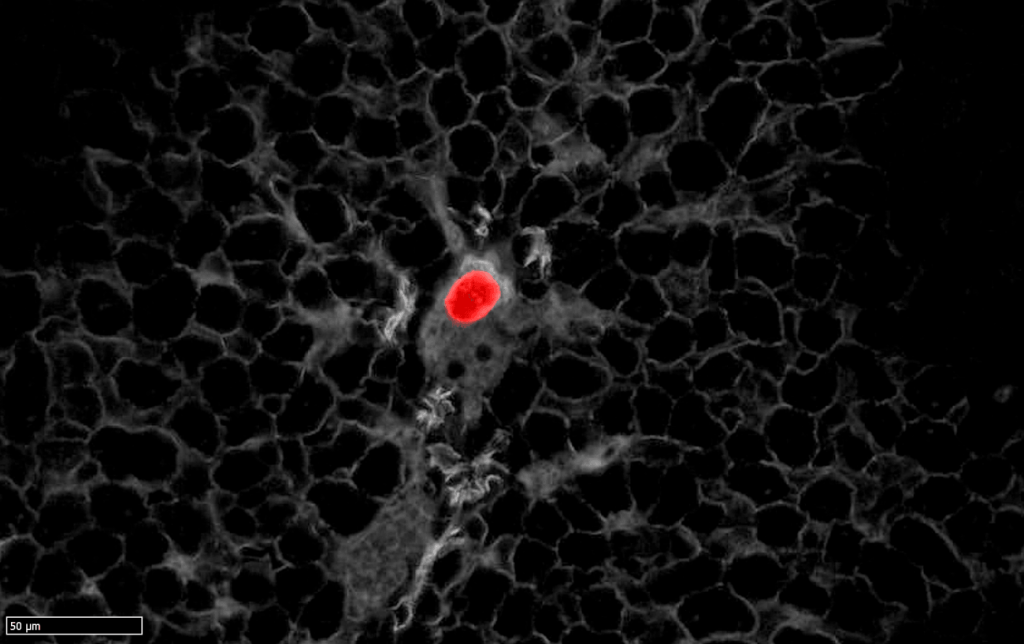

Estas células presentan poca actividad proliferativa y no contribuyen al crecimiento del tumor primario. Sin embargo, grupos de HRC son capaces de desprenderse del cáncer en el colon, migrar hasta alcanzar el torrente sanguíneo, llegar al hígado y permanecer ocultas durante un tiempo tras la cirugía. En muestras procedentes de pacientes con cáncer de colon los investigadores han podido constatar la presencia de estas mismas células en los pacientes que tienen un mayor riesgo de recurrencia de la enfermedad después del tratamiento.

Los investigadores además han confirmado que, eliminar estas células mediante técnicas genéticas es suficiente para prevenir la formación de metástasis; es decir, los ratones que desarrollan cáncer de colon se mantienen libres de enfermedad tras la cirugía del tumor primario, sin sufrir posteriores recaídas.

El equipo también ha desarrollado una estrategia terapéutica para erradicar específicamente la enfermedad residual y prevenir la recurrencia. Así han demostrado que las metástasis incipientes, cuando todavía no son visibles, pueden eliminarse mediante un tratamiento con inmunoterapia, previo a la cirugía.